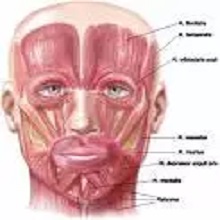

Тортиколис је накренутост главе на једну страну. Може бити урођени и стечени. Урођени се јавља због скраћења једног од вратних мишића ( „m. sternocleidomastoideus") најчешће као последица положаја бебе у стомаку мајке током трудноће. |